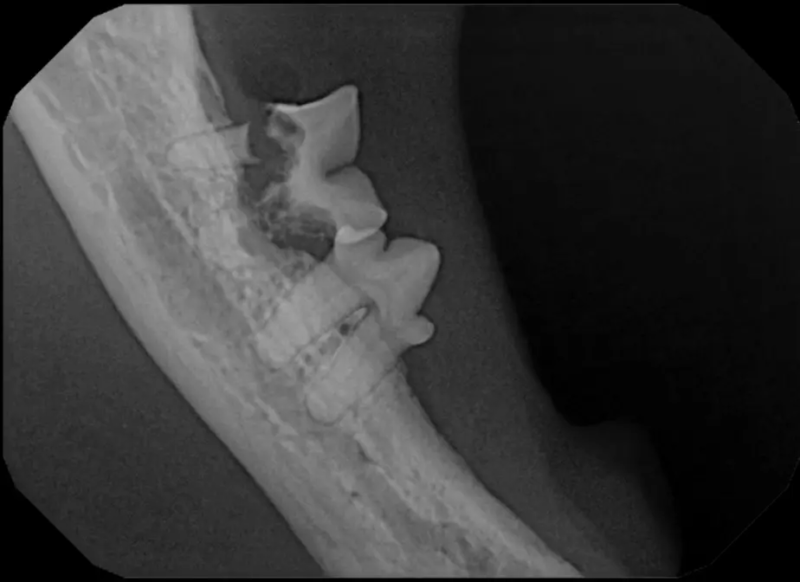

Repair of Maxillofacial Fracture

Pets can be involved in trauma that can cause fractures to their head, teeth, and jaw bones. Correctly repairing these fractures is extremely important for your pet to have normal function of their mouth. If a jaw fracture is allowed to heal in an abnormal position, your pet may have great difficulty chewing and can be in significant pain. Many fractures can be successfully treated with minimally invasive oral procedures, but more complicated cases may require bone plating techniques. The Center offers cone beam CT imaging which provides extremely detailed images of the bones of the head and skull. Advanced imaging with CBCT facilitates selection of the best surgical technique to get your pet back to eating and comfort as soon as possible.